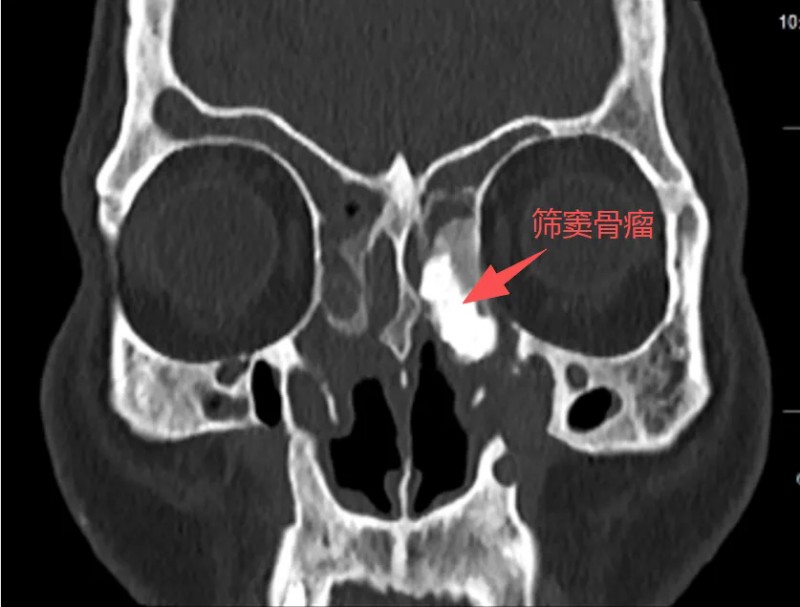

听完病史,王浩心里已经有数。但当他看完影像学检查结果,表情变得凝重起来。张大爷的情况远比普通鼻窦炎复杂得多:双鼻甲肥大,鼻中隔偏曲、鼻道里长满息肉样新生物。最棘手的是左筛窦发现一个巨大占位——高度怀疑是骨瘤,大小约3×4厘米。

术前

“骨瘤本身多为良性,但长在这个位置,就成了一个‘定时炸弹’。”王浩指着影像片子,向患者解释。

筛窦,是鼻腔深处一个结构极其复杂的区域。它的上方是颅底,隔着一层薄薄的骨头就是大脑;外侧是眼眶,视神经、筛前动脉等重要结构都在这里穿行。张大爷的这颗骨瘤,恰恰嵌合在眶内壁上,紧贴着这些要害部位。

如果不手术,骨瘤继续长大,压迫视神经可能导致失明,侵蚀骨壁、压迫颅脑组织可能引发更严重的后果;如果手术,筛窦区域解剖复杂,被称为“耳鼻咽喉科手术的珠穆朗玛峰”,稍有不慎,就会因伤及周围血管、神经、脑膜等出现大出血、视力减退甚至失明、脑脊液漏、颅内感染等严重并发症。